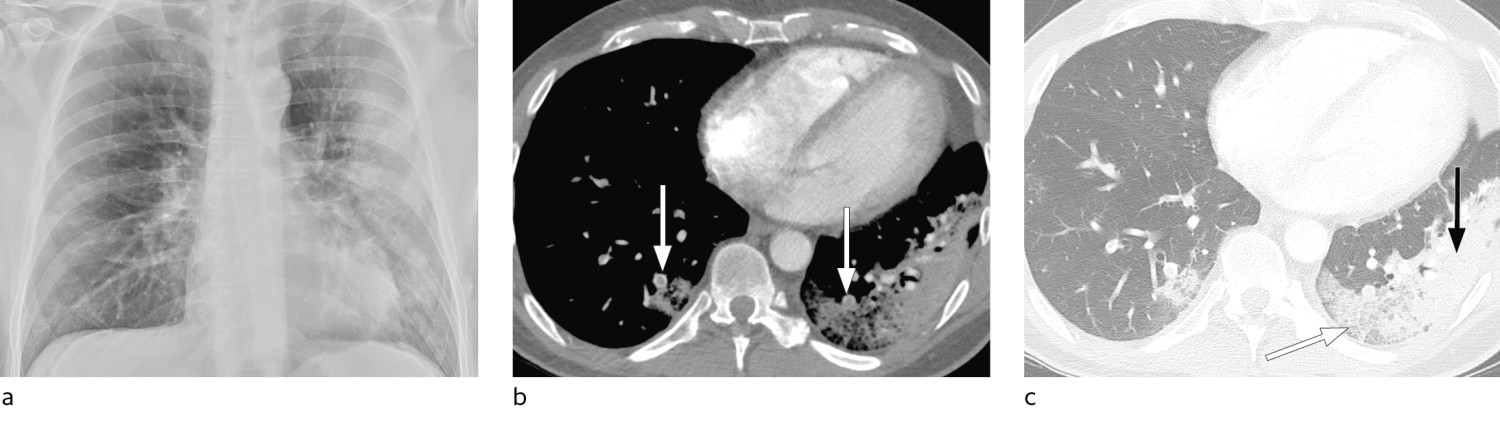

I et materiale fra Hongkong hadde 69 % funn på røntgen thorax før behandling (baseline), men 9 % hadde funn på røntgen thorax før positiv PCR (14). Sensitiviteten for røntgen thorax var 69 % og for PCR 91 %. Vanligste røntgenfunn var bilateral konsolidering og mattglassfortetninger med perifer og kaudal distribusjon. Forandringene var mest uttalt 10–12 dager etter symptomdebut. Figur 1 og figur 2 viser typiske funn på røntgen thorax ved covid-19.

Typiske CT-funn varierer med symptomvarighet og kan deles i tre stadier: en tidlig fase, en intermediær fase som strekker seg fra 3–5 dager etter symptomdebut, og en senfase. Det er ikke alltid funn på CT de første dagene etter symptomdebut. I et materiale med symptomatiske, men uspesifiserte pasienter hadde 56 % normale funn på CT innen to dager etter symptomdebut (12), avtakende til 9 % 3–5 dager etter symptomdebut og 4 % 6–12 dager etter symptomdebut. Funnhyppighet varierer med sykdommens alvorlighetsgrad. Ved første gangs bildediagnostikk var det normale funn hos 18 % i en gruppe pasienter med ikke alvorlig sykdom, men hos bare 3 % av pasienter med alvorlig sykdom (15). Typiske CT-funn er multiple, bilaterale mattglassfortetninger med perifer distribusjon, hyppigst lokalisert i underlappene. I intermediær fase er det økende innslag av konsolidering (tette infiltrater) og affeksjon av flere lapper samt økt septering med brosteinsmønster (crazy paving) som tegn på interstitiell affeksjon. I senfasen er det økende total utbredelse, men mattglassfortetninger og konsolidering er fremdeles dominerende funn (12, 16). Figur 4, figur 5 og figur 6 viser typiske funn på CT i ulike faser av covid-19.

Hos pasienter med akutt lungesviktsyndrom (ARDS) kan CT gi nyttig informasjon om tilgjengelig, ventilerbart lungevolum for å optimalisere ventilering (31, 32), og det kan være vesentlig å avklare eventuelle bullae eller pneumothorax. Hos pasienter med bekreftet covid-19 kan CT være indisert ved mistanke om komplikasjoner som lungeembolisme eller superinfeksjon (figur 7) og i oppfølging av uavklarte funn på røntgen thorax.